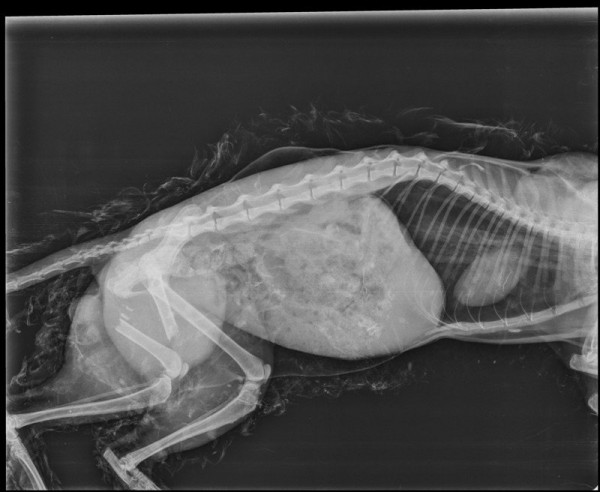

сегодняшний рентген. 18.11.17. Результат налицо !

Появился у нас на работе, на стройке кот. Откуда пришел неизвестно. Прятался под вагончиками и жалобно мяукал. Ну и подкармливал я его иногда. А тут иду раньше обычного в вагончик и вижу собаки бегают с лаем. Я и понять то толком не успел что происходит, вижу как одна собака ныряет под вагон и вытаскивает котейку ! Естесственно сразу, не раздумывая бросился его спасать. Схватил палку и отбил у них кота ! И вот, принес я его к своему вагончику. Жаль сфоткать не сообразил. А он весь в глине, грязи испачкан, собака его изваляли всего, воняет аж пипец ! За вагонами работники ссут, и представляете в этом дерьме они его изваляли ! Дальше все просто. Звоню своей девушке, говорю " Помнишь, про котика рассказывал ? Так вот, его разорвали на части. Будем спасать ? " Ее ответ был предсказуем " Конечно ! " И вот, вызвал такси, по пути забрал девушку, едем. От кота вонь, капец, водитель все окна открыл даже ! Привезли в клинику сделали рентген и оставили в стационаре. Оставил 2000 рублей и уехали домой. Через 2 дня приехали забирать. Заплатил еще 2 тысячи, и стали готовить его дома к операции. За операцию запросили еще 4 тысячи. И вот тут я обратился в зоозащитную организацию. Ну не потянуть мне такие расходы. Те согласились помочь с операцией. Дальше началось самое интересное. Вскрыли котику лапку, там гной и пошло-поехало. Отлежал он у нас в стационаре почти месяц, капельницы , уколы...Кровь была плохая, переливание крови даже делали )) Да!! котам кровь переливают также, как и людям !И по тихоньку кот стал выздоравливать. Впереди предстояла операция. После стационара, забрали его к себе домой, прокололи антибиотики и сново увезли на операцию. Она прошла успшно. В лапу вставили металлический штырь, раздробленные кости подпилили. Теперь кот и ходит и уже прыгает немного. Сегодня сделали рентген . Лапка сраслась хорошо. Хочется сказать спасибо всем неравнодушным людям, кто помог котейке. Таксистам что везли нас в клинику и потом домой. Кот вонял тогда жутко, один таксист чихал от вони и слезы текли из глаз ! Спасибо тебе мужик, что не высадил нас на полпути ! Спасибо людям, что приносили корм. Он, есть спец корм, стоит дорого,1000 кг. Спасибо всем врачам кто боролся за его жизнь. Сейчас у кота новая жизнь. Мы найдем ему достойных хозяев, кто будет его любить. А кот, к слову, очень ласковый, добрый. И все бы, ребят , хоршо, но одно НО ! Зоозащитная организация https://vk.com/zookorolevstvo лечила котика в долг. За лечение клиника выставила сумму почти 30 тысяч рублей ! Это не считая, что я своих 4 заплатил. Для них это очень большая сумма. Люди конечно помогают, но долг все же большой. Поэтому, от лица Зоокоролевства прошу помощи. Кому не жалко переведите им на карту, хоть 100, хоть 50 рублей. Вместе мы насобираем и сможем закрыть долг. Вся история лечения кота открыта в группе https://vk.com/zookorolevstvo начинать смотреть с начала, это примерно 21 сентября. перевод лучше сделать с пометкой " от фишек " чтоб знали .Это мой первый пост, возможно немного коряво получилось. На все вопросы готов ответить в комментариях.